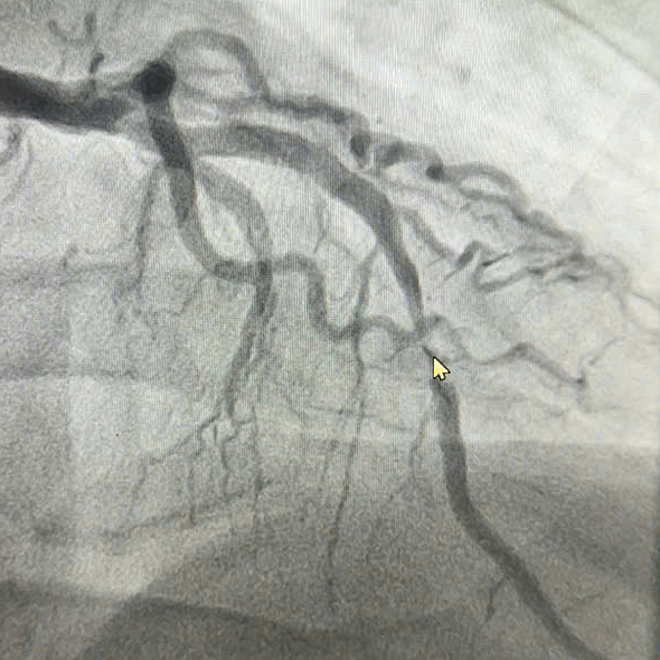

Ngày 5/11,đại diện Bệnh viện Đa khoa Hùng Vương cho biết người bệnh tiền sử tăng huyết áp,có thói quen hút thuốc lá để giảm căng thẳng. Khi vào viện,bệnh nhân đau ngực dữ dội. Từ kết quả điện tim và triệu chứng lâm sàng,bác sĩ chẩn đoán nhồi máu cơ tim cấp,động mạch liên thất trước (LAD) bị hẹp tới 99% do huyết khối.

Nhận định tình trạng khẩn cấp,êkíp can thiệp đặt một stent phủ kín vùng tổn thương để dòng chảy qua động mạch vành của bệnh nhân tái thông. Sau can thiệp,tình trạng đau ngực giảm rõ rệt.

Hình ảnh động mạch hẹp trước khi can thiệp. Ảnh: Bệnh viện cung cấp